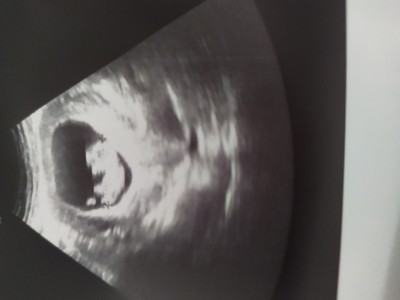

İlk hamileliğim kızdı çok kusuyordum ağrım vardı bunda hiç belirtim yok çok rahat geçiyor bakar mısınız cinsiyete

Gebelik haftası 16

Cuma günü gidecem ama merak ediyoruz işte her anne gibi bu 12 haftalık görüntüsü

benim bebegimin ultrason resmi ile kıyaslıyorum ve benzetiyorum büyük ihtimalle erkek :)

Bizimki böyle idi erkek sandjm 1 hafta sonra kız dediler çıkıntı okuyor ilk başlarsa öyle

Valla benim  de ilk oğlan  hamilelik belirtileri aserme falan filan hepsi aynı oglumdaki gibiydi erkek dediler bu da kesin bide sağa yerleşmiştir herkes erkek bekleri ultrason 11 haftada aynı bu şekil çıkıntılı gördüm  kesin erkek dedim yumurtaliklari sanki yuvarlak yuvarlak 1 hafta sonra tekrar bakıldı kızmış şu an 18 haftayiz halen kız diyorlar bula bilsem resim  atarım aynı bu şekilde ama  sizin erkek ola bilir kesin kiz diyemem Dr değiliz:) benimkine benzedi diye dedim

İki tane crl var ustekinde 9.80cm altakinde de 3.74 cm yazıyor

Foto çok net değil ama benim anladığım nuba göre erkek, tabi öncelikli sağlıklı ve hayırlı bir evlat olması, sağlıkla kucağınıza alın inşallah